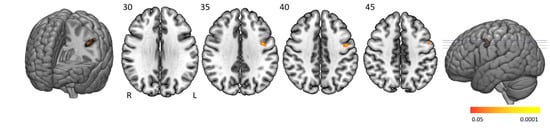

3.3. Main Task Effects

The “task > baseline” contrast elicited significantly stronger BOLD activation in the cingulo-opercular network, arousal system, motor (regulatory) areas, and visual cortex (Figure 3 and Table 2). The cingulo-opercular network was activated by means of the bilateral insula, thalamus, anterior cingulate cortex, and the right middle frontal gyrus. Other attention-regulation-related areas included the bilateral midcingulate cortex, right intraparietal sulcus and left inferior parietal gyrus being part of the frontoparietal network, vermis and bilateral inferior orbitofrontal gyrus, and fusiform gyrus. Motor (control) areas comprised the left pre- and postcentral gyrus, bilateral supplementary motor area, putamen, and cerebellum. The bilateral red nucleus, substantia nigra, and locus coeruleus within the midbrain and pons were also activated, with the pons being fundamental in managing arousal and attention. Task activation patterns of healthy controls and people with narcolepsy type 1 were similar and no significant main task effect differences were present between groups. No significant group differences were seen on the “baseline > task” and “higher difficulty level > moderate difficulty level” contrasts.